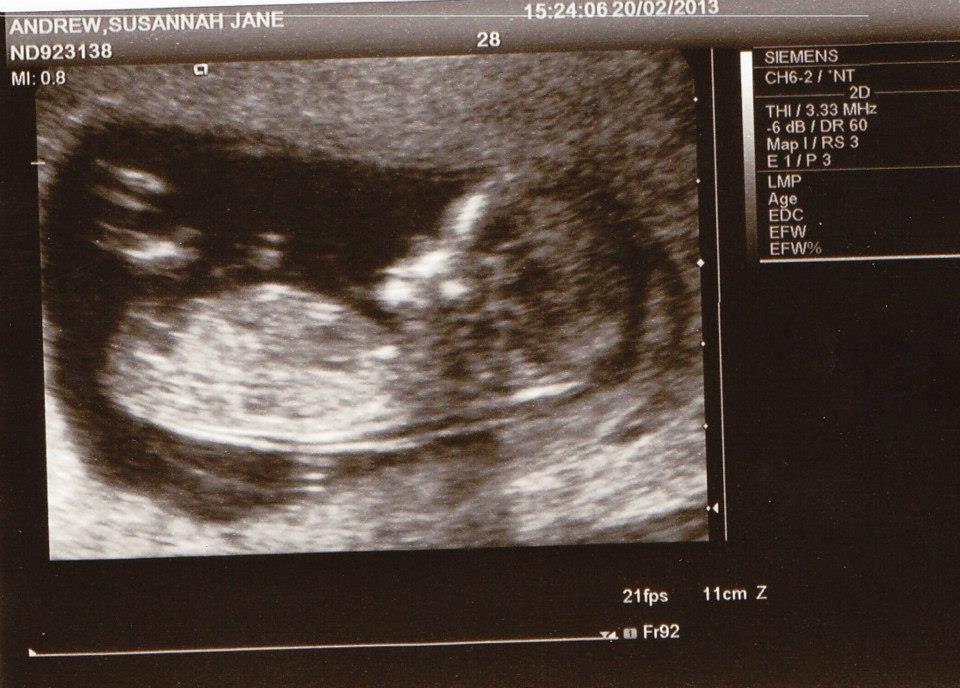

These are for a friend. They were both taken on the same day at 12 weeks 5 days. Is there a nub visible? Would appreciate any guesses.

Attachment 9108

I don't see a nub.

Maybe girl, but it's only a guess

I can't see a nub but can see other things that make me think girl (shape down there).

no nub :(

Thanks girls. I'm leaning girl aswell. I couldn't see a nub either, although think I may be able to see part of it. She has one boy already and her 12 week scan with him was completely different, clear boy nub and the scull shape is completely different.

i don't think i see a nub.